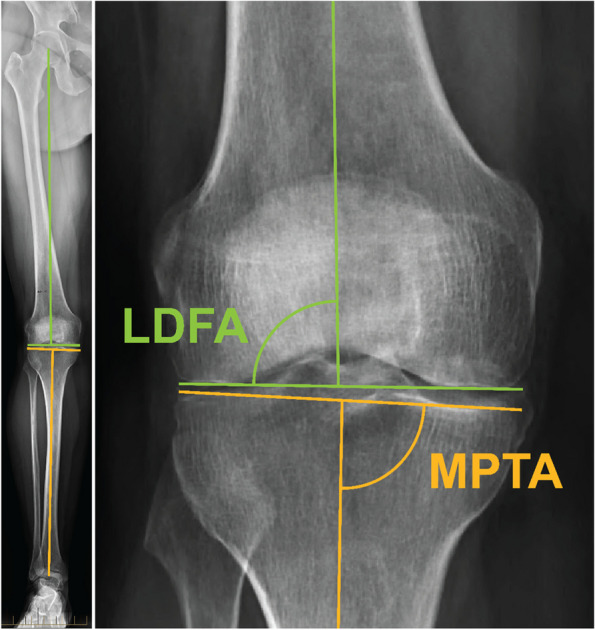

Methods: Medial proximal tibial angle (MPTA) and lateral distal femoral angle (LDFA) were determined from the intraoperative registration data of 61 imageless robotic TKAs using either a generic 2 mm literature-based wear assumption (Navlit) or an optimized wear assumption (Navopt) found using an error minimization algorithm. MPTA and LDFA were also measured from preoperative LLR by two observers and intraclass correlation coefficients (ICCs) were calculated. MPTA, LDFA, joint line obliquity (JLO), and arithmetic hip-knee-ankle angle (aHKA) were compared between the robotic and the average LLR measurements over the two observers.